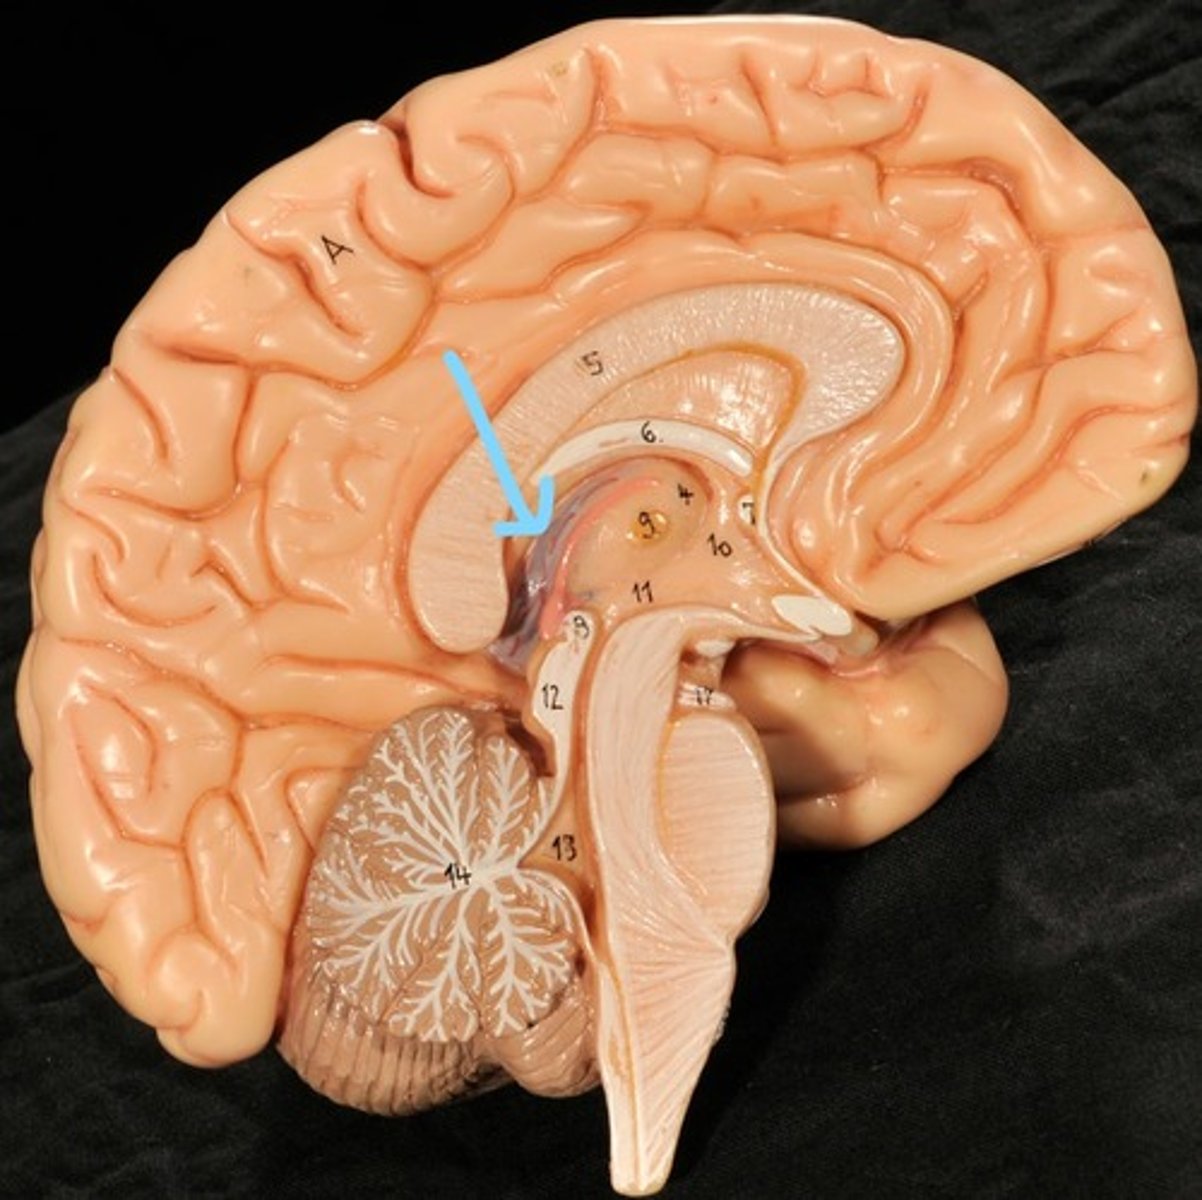

Identify structures of midsagittal brain

Corpus callosum

Diencephalon

thalamus, third ventricle, hypothalamus, epithalamus

Thalamus

Third Ventricle

Hypothalamus

Epithalamus (pink line)

Brain stem

Pons

Medulla oblongata

choroid plexus of third ventricle

produces cerebrospinal fluid

Third ventricle

cerebral aqueduct (midbrain)

midbrain

Fourth ventricle

Central Canal of brain

Takes Cerebrospinal fluid down to the spinal cord

Thalamus